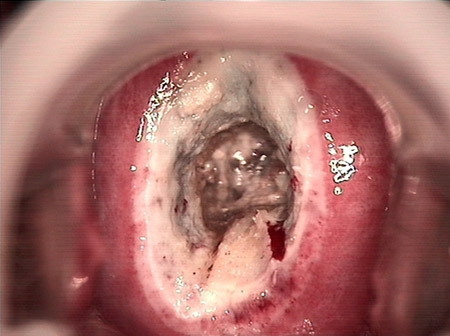

婦科leep錐切手術(shù) CIN2-3

CIN 2-3 碘著色后

CIN 2-3 leep術(shù)后